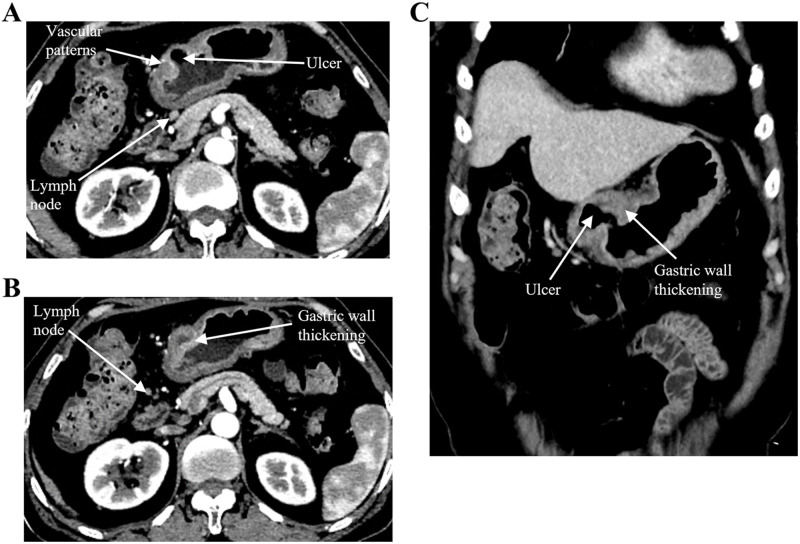

Post-transplant lymphoproliferative disorder (PTLD) is a rare complication following hematopoietic stem cell transplantation (HSCT), with its occurrence post-autologous hematopoietic stem cell transplantation (auto-HSCT) being even rarer. Research on PTLD following auto-HSCT is exceedingly scarce. Here, we present a noteworthy instance wherein a patient with diffuse large B-cell lymphoma (DLBCL) developed PTLD, manifesting as classical Hodgkin lymphoma (cHL) two years after auto-HSCT. Additionally, we conducted an extensive review of existing literature, exploring the current research on PTLD following auto-HSCT and illuminating this scarcely examined area.